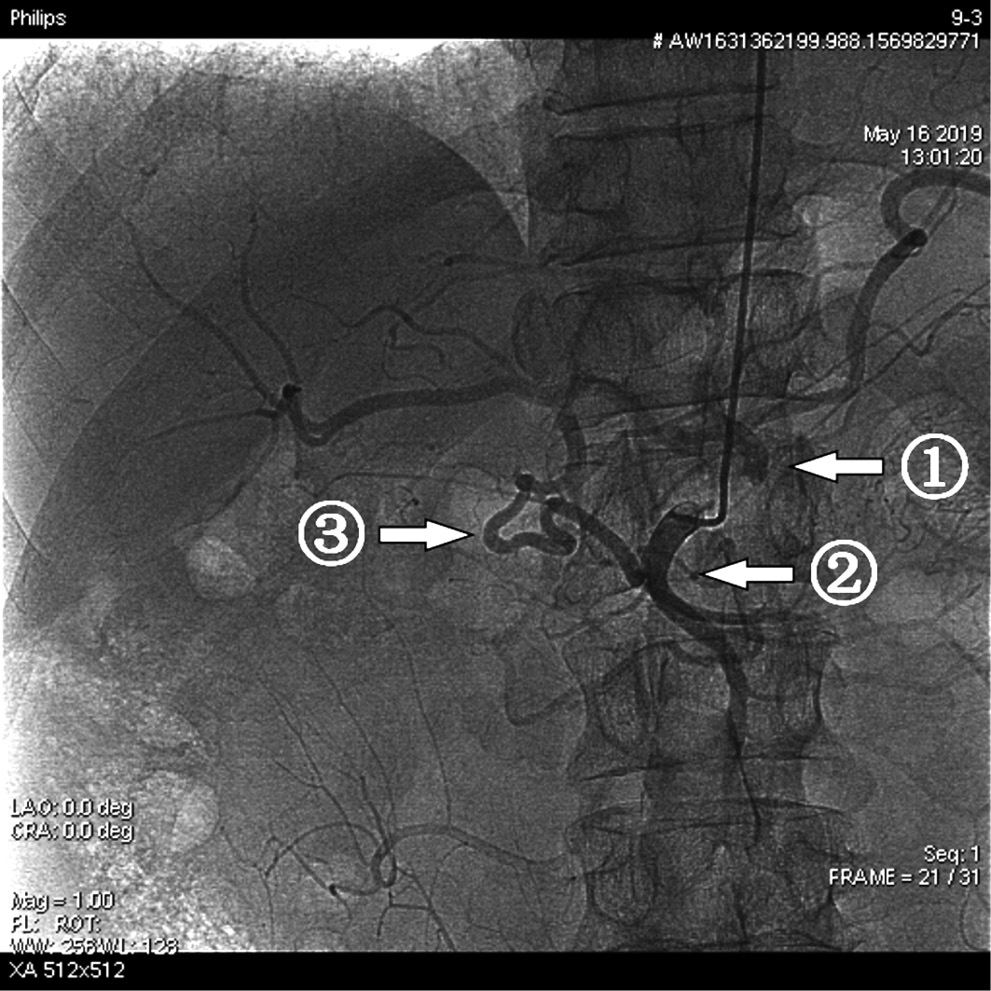

Микрокатетерная техника ХЭПА повышает вероятность выполнения запланированного объема вмешательства еще и потому, что хорошо профилактирует возникновение интраоперационных осложнений в бассейне чревного ствола. Так, при выполнении монолобарной ХЭПА после селективной катетеризации правой печеночной артерии катетером 5F на контрольной целиакографии был визуализирован выраженный спазм правой печеночной и собственной печеночной артерий (рис. 5, 6).

Рис. 5. Исходная целиакография: сложности катетеризации сегментарных ветвей печеночных артерий при развитии спазма

Примечание. 1 — собственная печеночная артерия, 2 — правая печеночная артерия, 3 — левая печеночная артерия.

Рис. 6. Контрольная целиакография после селективной катетеризации правой печеночной артерии: сложности катетеризации сегментарных ветвей печеночных артерий при развитии спазма

Примечание. 1 — спазм собственной печеночной артерии, 2 — спазм правой печеночной артерии.

Такие интраоперационные осложнения, как спазм артерий, их диссекции и окклюзии, нередко наблюдаемые у пациентов при традиционной методике выполнения ХЭПА, ни разу не встретились при ХЭПА с использованием микрокатетерной техники. Таким образом, при проведении химиоэмболизации артерий печени у пациентов с нерезектабельным метастатическим раком печени большое значение имеет диагностический этап висцеральной ангиографии, направленный на оценку варианта кровоснабжения печени у конкретного пациента, а также выявление индивидуальных особенностей состояния сосудов или реактивного ответа со стороны сосудов в виде спазма на введение инструмента и контрастного вещества.